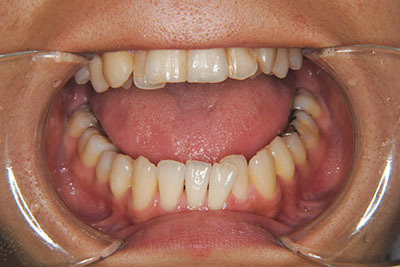

おとなの方でも矯正治療をあきらめないでください!

いくら歯が動き易くとも、本人がやる気でなければ効果は出ませんし、むし歯発生のリスクも高まります。おとなの方は顎の成長が終わっているため、治療の計画が立てやすいとも言えます。「もう大人だから…」とあきらめず、一度ご相談ください。